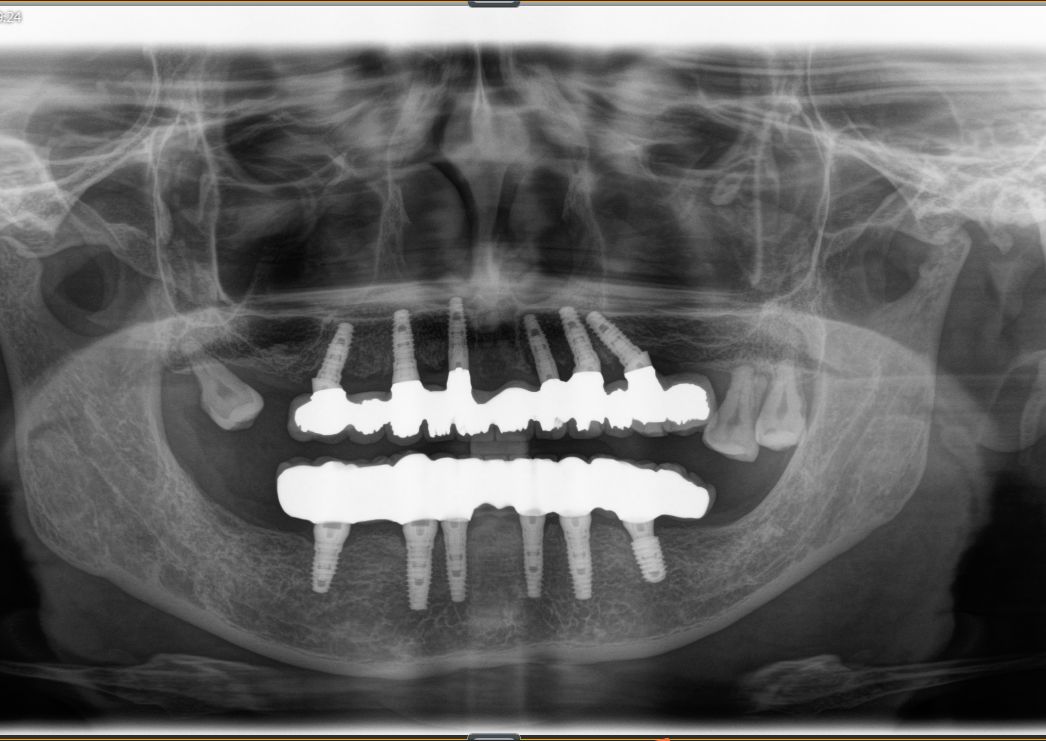

这是一位今天种植牙复诊患者的牙齿的,早期因为牙齿缺失和牙齿松动,严重影响美观,更影响了她的饮食,15年前我为她种了上半口,一直用得很好!但下合的牙因重度牙周病引起牙齿松动和脱落,今年我又为她种了下半口;经过采用种植牙的方式,使得她的牙齿重换新生,患者说:“戴上牙以后什么都能吃,体重还重了许多,很庆幸当时选择种牙这个选择”。

术后图片